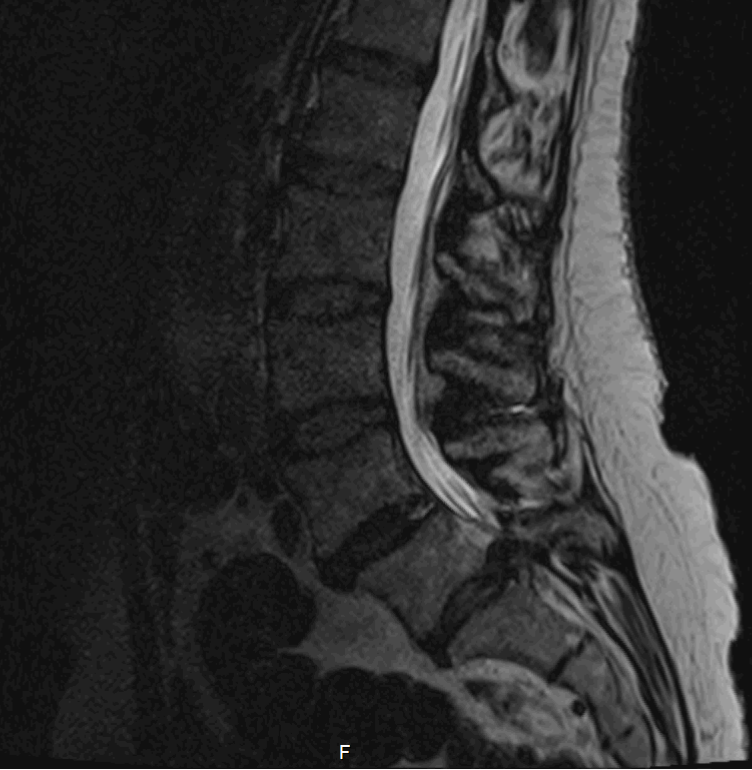

T2-viktad MR av cauda equina L5-S1